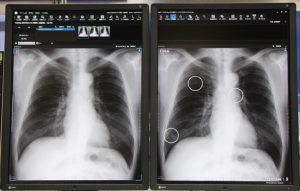

専門家医のスキルをディープラーニングで事前学習したAIが胸部X線画像を解析する、胸部に特化した画像診断支援AIソフトウエア。医師による読影に際し、結節影や浸潤影、腫瘤影など、肺癌や肺炎、結核などに繋がる所見を検出するソフトウエア。読影時にAI解析結果を確認することで、見落とし防止が図れるだけでなく、撮影後、医師の読影結果とAI解析結果を突き合わせることで、確信度の向上にもつながる。

AIによる検出感度は、結節・腫瘤影で約83%、浸潤影で約80%。また、読影時、AI画像診断を用いた場合、経験が5年以下の医師の平均感度は約67%から約79%に。6年以上の経験を有する医師でも、約81%から約85%に向上するとの実験結果がでているので、若手技師の研修などでの活用も期待できる。

胸部X 線画像診断支援AI ソフトウェアCXR finding-i